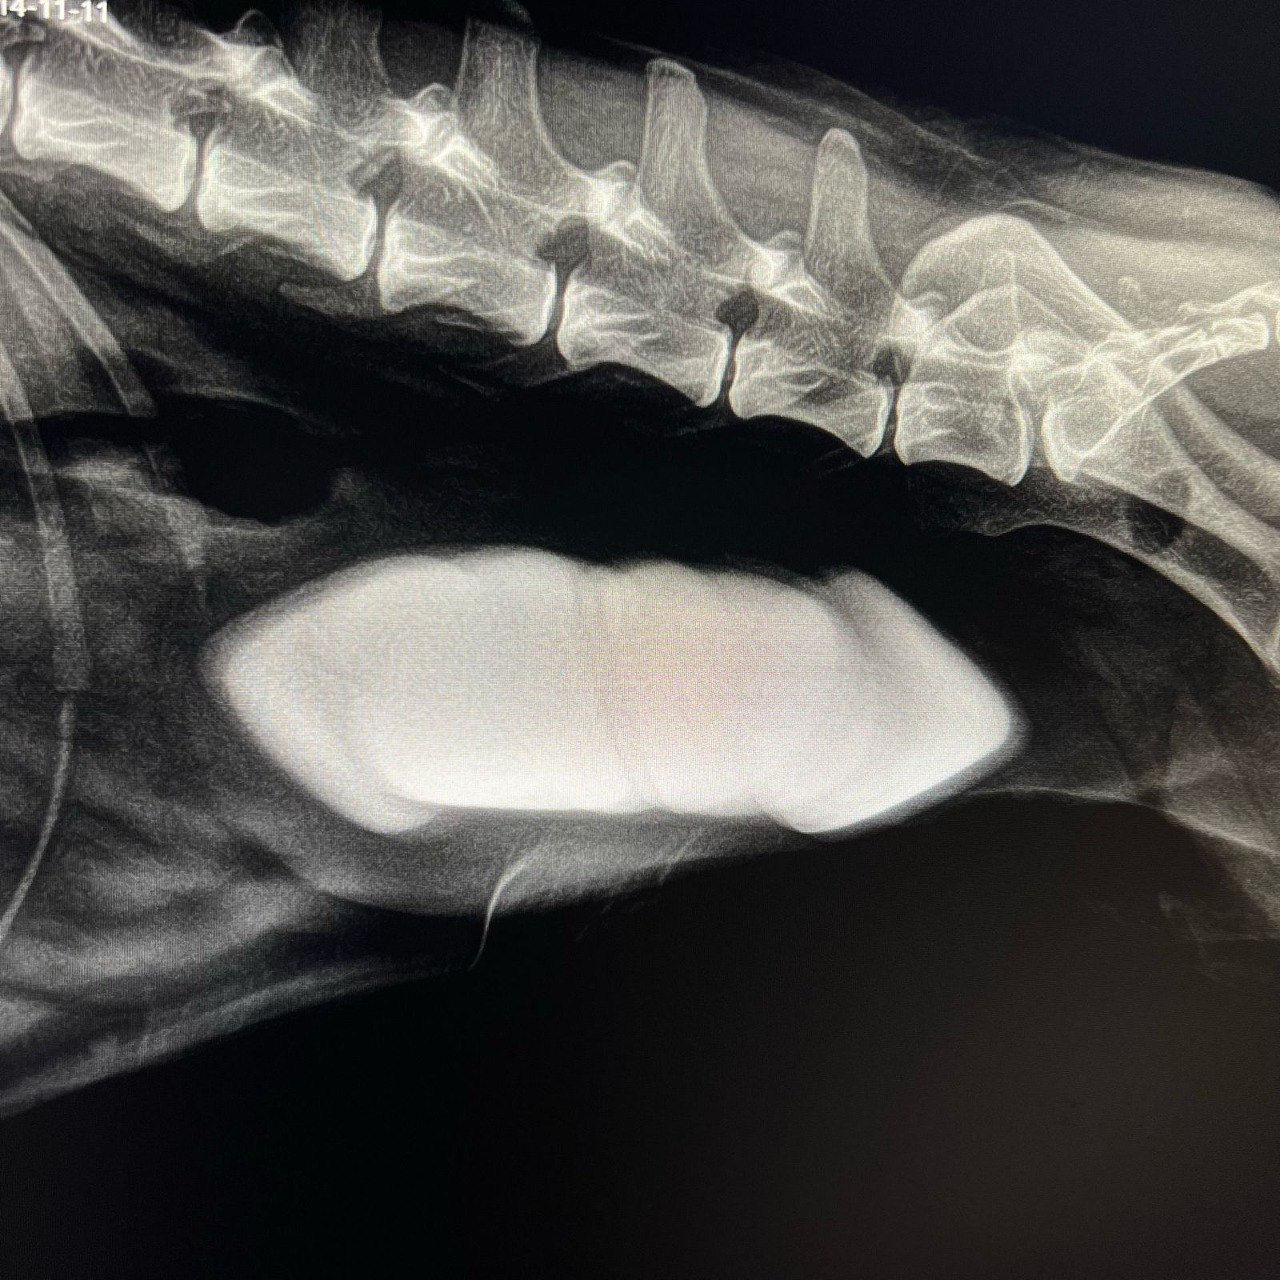

Рентген-аппарат нового поколения спас жизнь 10-летней собаке Торе!

Обследование показало, что в организме животного находились 7 гигантских камней. Вологодские ветеринары успешно прооперировали Тору и сейчас жизни собаки ничто не угрожает, сообщает Минсельхоз региона.